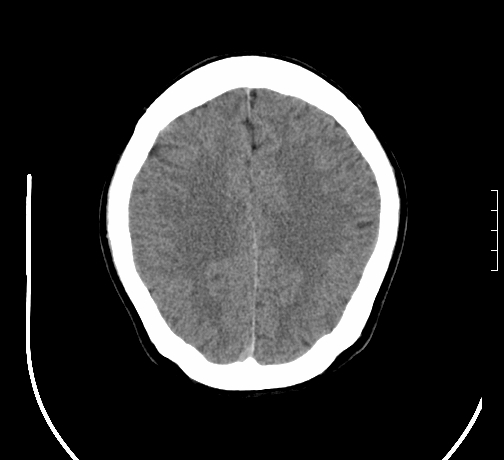

小脑发育畸形?

小脑萎缩。

考虑小脑发育不良,建议mri检查。

考虑小脑发育不良伴小脑萎缩,建议mri检查。

考虑小脑发育不良伴小脑萎缩,建议mri检查

考虑药物性小脑萎缩